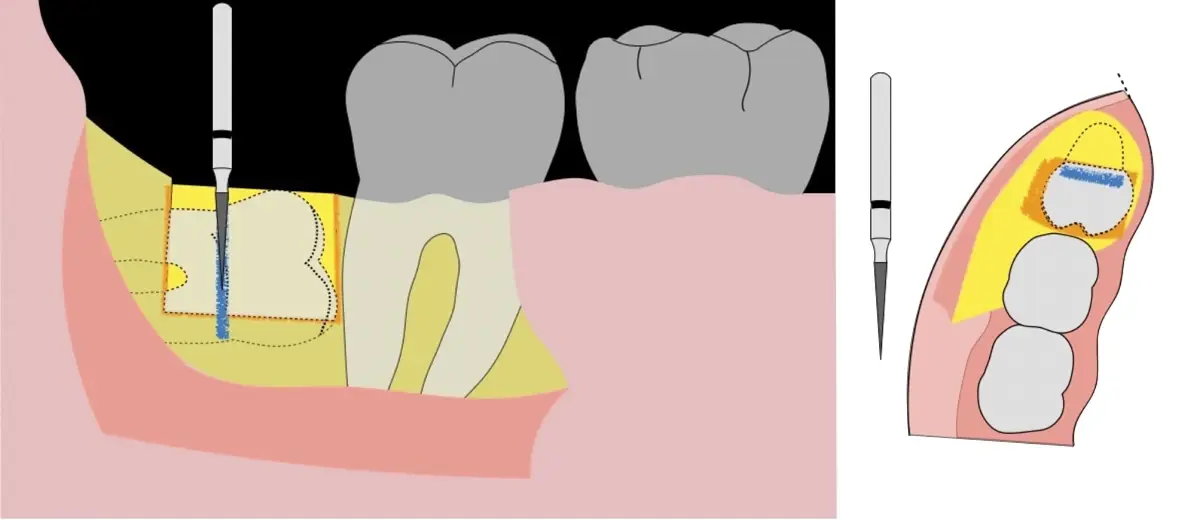

Figura 4. Demarcación de la zona de osteotomía con insertos de corte recto y/o angulado a nivel oclusal. Vista frontal (a). Vista oclusal (b).